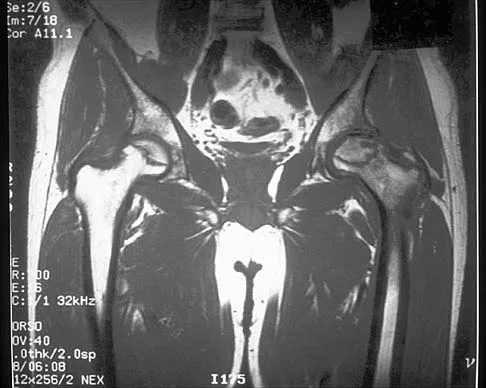

Figure 37 shows the T2-weighted MRI scan of the hip joint. What structure is labeled A?